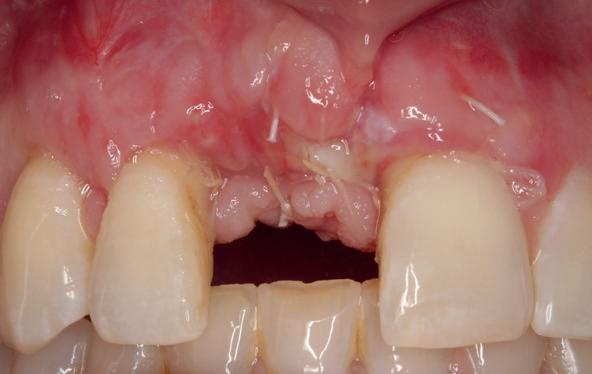

Implantologische behandelingen in het esthetische front vragen meer dan technische vaardigheid alleen. Ze vragen om overzicht, timing, vertrouwen en een team dat als vanzelf samenwerkt onder druk. Juist bij complexe casussen, waarin angst, infectie en hoge esthetische verwachtingen samenkomen, wordt zichtbaar hoe bepalend de rol van de tandartsassistent is.

Deze casus beschrijft een uitgebreide immediate implantaatbehandeling bij een patiënt die door meerdere collega’s werd geweigerd. Niet omdat de mogelijkheden ontbraken, maar omdat de complexiteit vroeg om een perfect afgestemde samenwerking. Het verhaal laat zien hoe de assistent in zo’n traject veel meer is dan een uitvoerende kracht of “mal”, maar een dynamische surgical guide die het proces mede stuurt, bewaakt en mogelijk maakt.De patiënt: wanneer alles samenkomt

Ze kwam binnen op een dinsdagochtend, iets voor achten. Een vrouw van begin zeventig, met een zachte stem en ogen die meer vertelden dan haar woorden. Ze vertelde dat ze een eigen B&B had en dat ze zich nauwelijks kon voorstellen gasten te ontvangen zonder tanden. Op dit moment kon ze echter nauwelijks lachen. “Het doet pijn… en het ruikt soms ook niet goed,” zei ze bijna verontschuldigend. Haar oude bovenbrug, die ze al meer dan twintig jaar droeg, was langzaam maar zeker ingestort. Er was sprake van cariës onder meerdere pijlers, pusafvloed,

chronische ontsteking en een brug die mobiel was en elke beet pijnlijk maakte. Ze had inmiddels meerdere tandartsen bezocht. Drie hadden haar geweigerd. Te complex. Te veel wensen. Te onvoorspelbaar.

De kern van haar vraag was eenvoudig en tegelijkertijd uitdagend: Is het mogelijk om mijn huidige brug te dupliceren en een nieuwe brug te vervaardigen met minder complicaties?

De basis van een complexe beslissing

Mijn behandelplan begint altijd met een uitgebreid klinisch onderzoek. Dat omvat een medische anamnese, intra- en extra-orale camerafoto’s en uitgebreid verwachtingsmanagement. In deze fase is mijn assistent vooral bezig met het zorgvuldig vastleggen van alle gegevens. Juist dat nauwkeurig documenteren zorgt voor rust in de behandelkamer. Minstens zo belangrijk is het luisteren naar de patiënt. Niet alleen naar de klachten, maar naar het

1. Extra-orale foto (lachlijn).

2. Beoordeling van zacht weefsel en botcontour.

3. Reflectiefoto – beoordeling van occlusievlakken en tandboog.

4. Pre-chirurgische OPG.

levensverhaal en de mens achter de brug. Begrijpen wat deze behandeling voor iemand betekent, is cruciaal voor het uiteindelijke succes.

Na het klinische onderzoek volgde het röntgenologisch traject. De CBCT liet precies zien wat we al vreesden: een front waarin het bot onregelmatig was, duidelijke radiolucenties rond de pijlers en een infectiegebied dat zich onder vrijwel de gehele brug had verspreid. Tegelijkertijd was er ook potentie. Net voldoende botstructuur om immediate implantaatplaatsing te overwegen, mits alles perfect gepland zou worden.